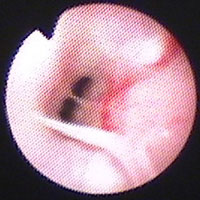

気管支鏡検査:第12病日に行った。肉眼所見で、肺内気管支粘膜に浮腫・軽度発赤あり(図5)、BAL[RB3, 10ml×3, 回収率77.3%]に好酸球数の増加(33.2%)とマクロファージの活性化がみられ(図6)、培養にて細菌も真菌も検出されなかった。

図5 症例2の気管支鏡検査所見。肺内気管支粘膜に浮腫・軽度発赤がみられた。